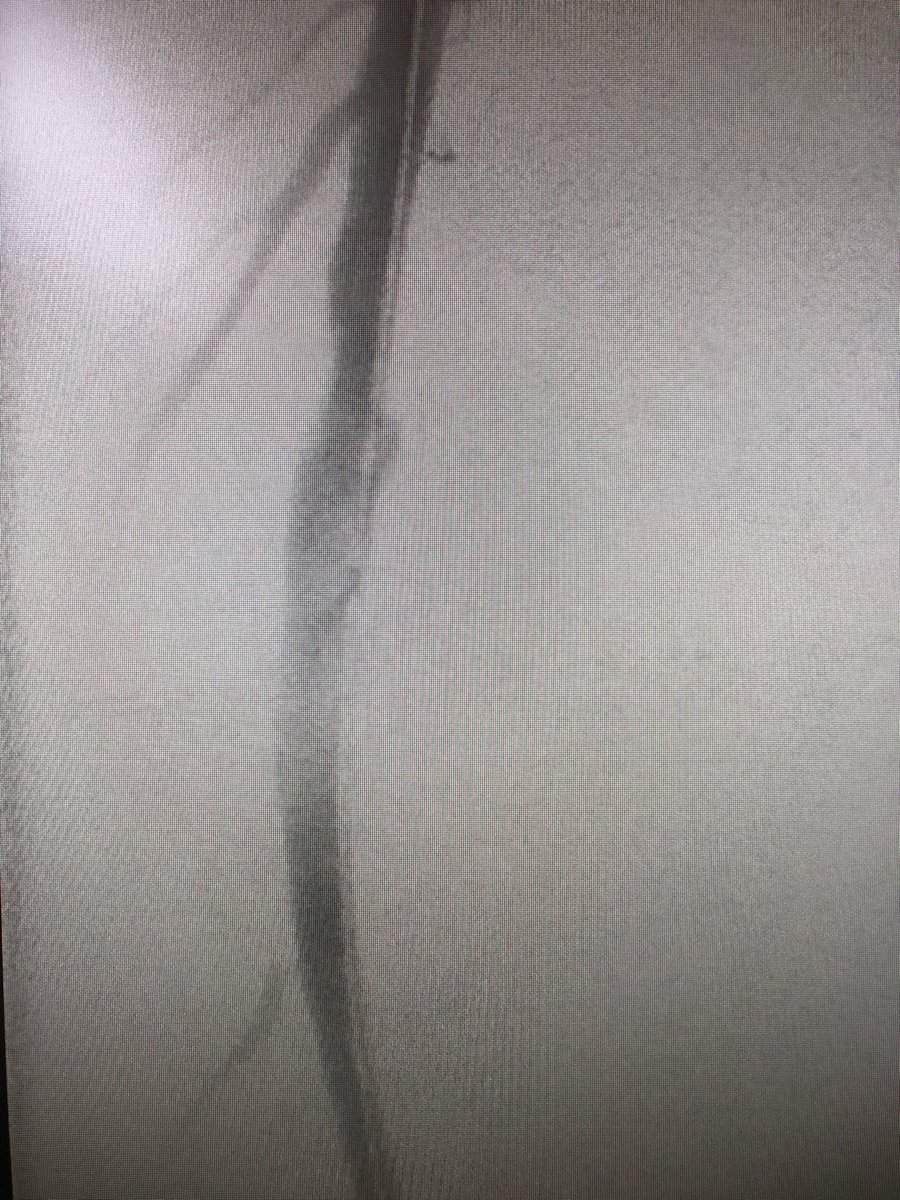

Step 3 - cautiously insert guidewire. #FluoroTheWire as it courses the artery. Observe its behavior and incorporate this into what sheath you should use for the procedure you need. I have started taking a quick #FluoroStore to show angle of needle and wire. #JointCathConference